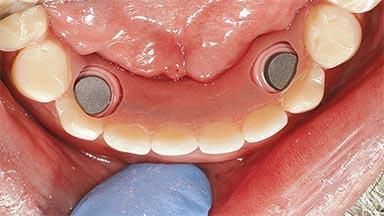

# of Implants 2

Type of Implants One-Piece

Attachment One-Piece

Prosthesis Type RDP

Defining Characteristics Fully edentulous lower jaw to be rehabilitated with an implant-borne removable overdenture